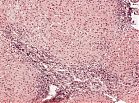

Histologie

• entzündliche Infiltration, v.a. im Bereich der Portalfelder

• fingerförmiges Übergreifen der Entzündung in das angrenzende Parenchym (Mottenfraßnekrosen)

• mononukleär demarkierte Zelluntergänge

• Faservermehrung

Mikroskopisch ist eine portalfeldbetonte mononukleäre Entzündung (Infiltrat: Lymphozyten, Histiozyten, Plasmazellen), die in Form sogenannter Mottenfraßnekrosen (Interface-Hepatitis) auf das benachbarte Läppchen übergreifen kann, erkennbar. Die Leberparenchymschädigung ist Folge einer Elimination infizierter Hepatozyten durch das Immunsystem. Eine beginnende Bindegewebsvermehrung (Fibrose) ist zu Beginn der Erkrankung fakultativ. Im Verlauf kommt es zur progredienten Fibrose bis hin zum zirrhotischen Umbau.